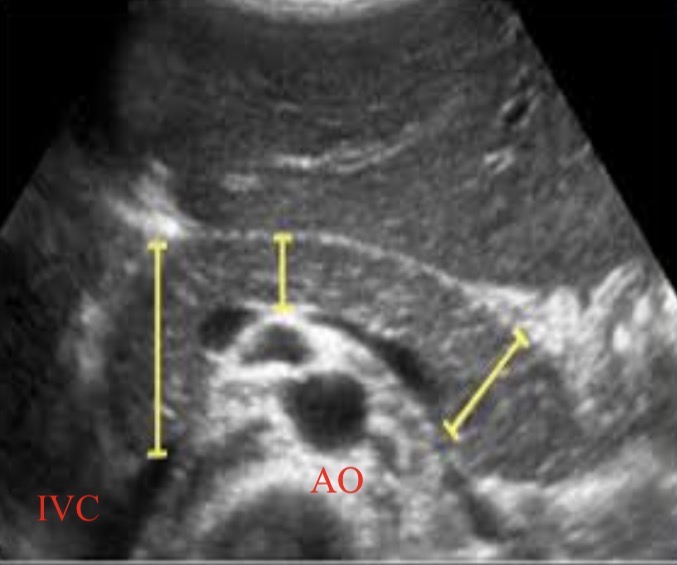

Size of head, neck, tail

Head<3cm

Neck<2.5cm

Body<2.5cm

Tail<2.0cm

Posterior vascular landmarks for pancreas

IVC and aorta